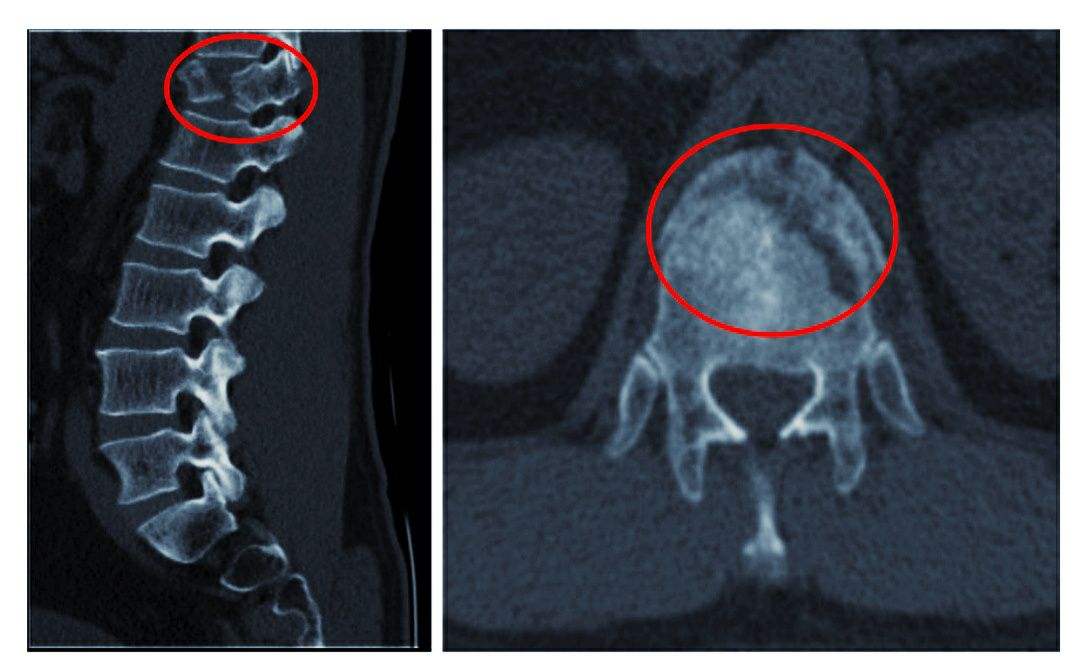

2、椎體緣、關節突、鉤椎關節骨贅形成

骨贅即骨質增生俗稱為骨刺,是指骨關節邊緣上由于長期慢性損傷引起瘢痕組織增生,天長日久可產生鈣質沉著變成骨質而形成的。

由于椎間盤的退變,其后果必然導致頸椎生理曲線的改變,破壞了椎體間的平衡。久之,機體為了抵抗疼痛,使神經免受刺激,建立新的平衡,而產生代償性骨贅,來穩定脊柱。當然骨贅形成的主要原因是急慢性損傷,骨贅的形態及部位與損傷的性質等有關,骨贅的大小與年齡有關,與癥狀的輕重不一定成正比。若骨贅發生于椎間孔或椎管附近,可產生神經根、椎動脈或脊髓受壓癥狀。